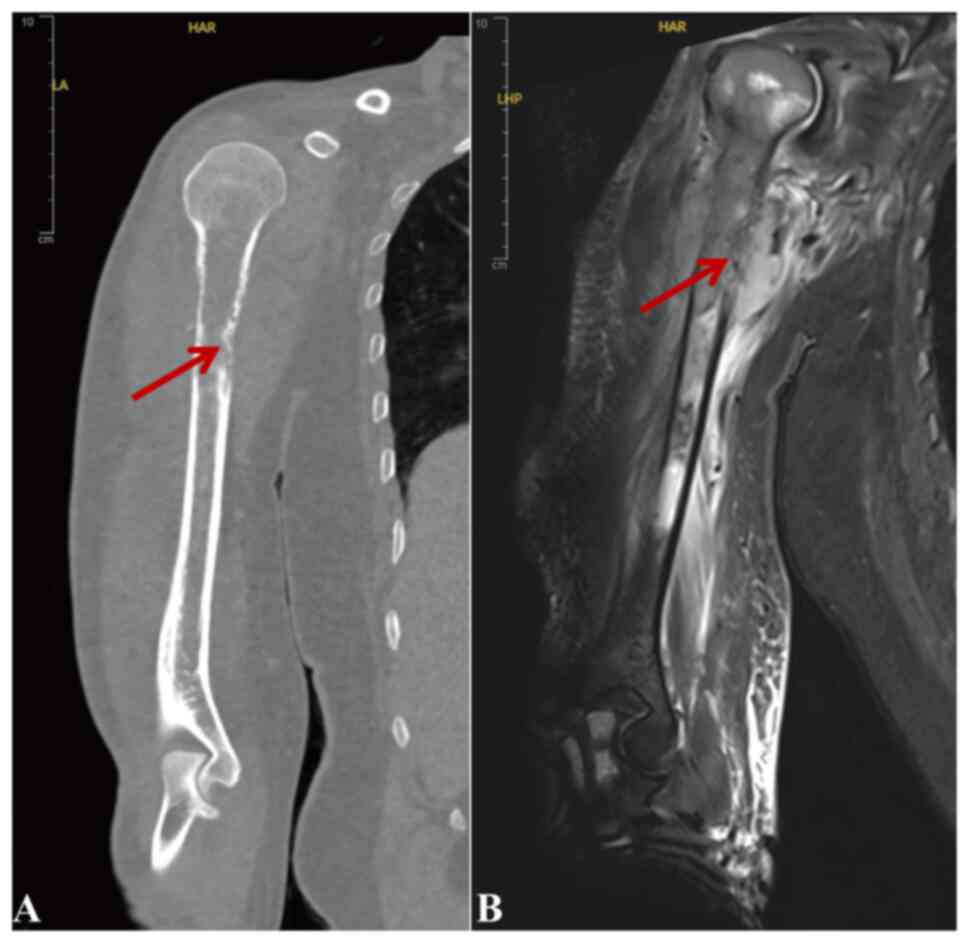

Imaging studies indicated malignancy in the right humerus, with computed tomography revealing bone destruction in the upper to mid humerus and localized lytic lesions in the scapula. Magnetic resonance imaging (MRI) demonstrated proximal humerus cortical disruption, heterogeneous signal intensities and surrounding soft-tissue masses with mixed high and low fat-suppressed T2-weighted imaging signals, consistent with a malignant process (Fig. 1A and B). The patient was started on dasatinib (100 mg once daily), with recommendations for regular blood count monitoring and surgical intervention after disease control. After 1 month of treatment, the patient achieved complete hematological remission, with notable improvement in arm pain. However, a biopsy was not performed during this period.

Imaging findings of the right

humerus. (A) Computed tomography showing bone destruction in the

upper to mid humerus and localized lytic lesions in the scapula.

(B) Magnetic resonance imaging revealing cortical disruption,

heterogeneous signal intensities and surrounding soft-tissue masses

with mixed high and low fat-suppressed T2-weighted imaging signals,

consistent with malignancy. The arrows indicate the lytic bone

lesion

Imaging findings of the right humerus. (A) Computed tomography showing bone destruction in the upper to mid humerus and localized lytic lesions in the scapula. (B) Magnetic resonance imaging revealing cortical disruption, heterogeneous signal intensities and surrounding soft-tissue masses with mixed high and low fat-suppressed T2-weighted imaging signals, consistent with malignancy. The arrows indicate the lytic bone lesion

Although the present imaging findings and clinical course suggest extramedullary leukemic infiltration, definitive pathological confirmation is essential to establish the diagnosis of blast-phase CML with extramedullary disease, which may have influenced the accuracy of diagnosis and subsequent treatment decisions. In the present case, using MRI, a large soft-tissue mass was observed encasing the affected bone, combined with cortical disruption and bone destruction, likely indicating leukemic cell infiltration. The soft tissue encasement of bone is consistent with previous reports of myeloid sarcoma in CML (48). These imaging findings are associated with the patient's persistent arm pain and elevated BCR-ABL1 transcript levels.